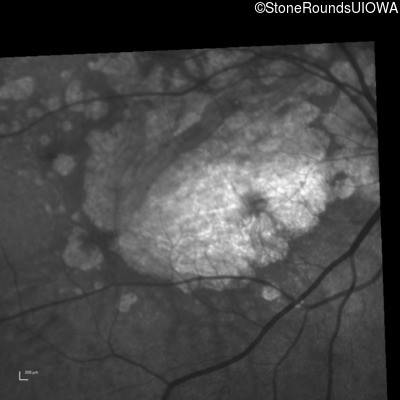

Blue Autofluorescence - Right - 3/100

Exemplar